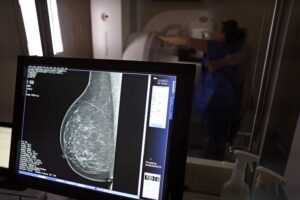

Teste de mamografia realizado na Campanha Outubro Rosa: Sesc-DF. Foto: José Cruz/Agência Brasil – José Cruz/Agência Brasil.

Um dos principais critérios é a realização de rastreamento organizado, ou seja, a convocação das usuárias para realizarem exames regularmente, mesmo sem sintomas. No caso do câncer de mama, a cartilha seguiu o protocolo do Ministério da Saúde e do Instituto Nacional do Câncer (Inca): mamografias a cada dois anos para as mulheres com idades entre 50 e 69 anos.

No Brasil, a cobertura da mamografia ainda é um desafio. A última Pesquisa Nacional de Saúde, realizada pelo Instituto Brasileiro de Geografia e Estatística (IBGE) em 2019, mostrou que menos de 60% das mulheres de 50 a 69 anos tinham feito mamografia há menos de dois anos da data da entrevista.

O parecer ressalta que o cenário do rastreamento é melhor na rede privada, onde “53% dos tumores são detectados pela mamografia, em pacientes assintomáticas, e 40,6% são diagnosticados no estágio I (menos agressivo)”, logo não há risco de prejuízo para as usuárias que já têm indicação, caso mais mulheres sejam incluídas.